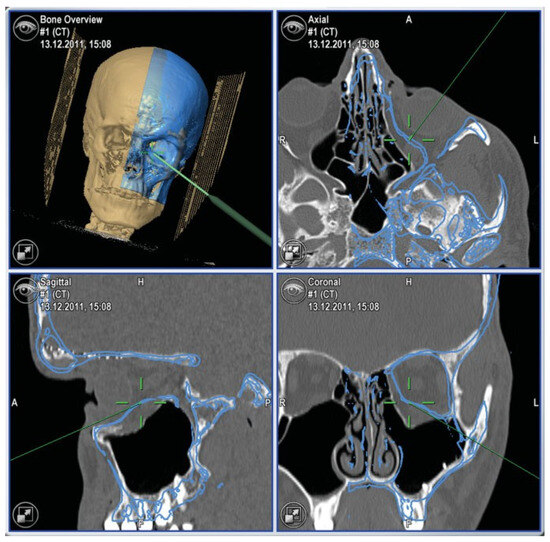

- Primary signs: fracture of the optic nerve canal; fracture in the retrobulbar region; hematoma, swelling, or disconti- nuity of the optic nerve; hematoma in the posterior third of the orbit.

- Secondary signs: shading of the sphenoidal sinus or of the posterior ethmoidal cells; air–fluid level in the maxillary sinus; epidural hematoma of the temporobasal region.

- Concomitant injuries: lamina papyracea; frontal sinus; zygomatic bone; orbital floor; orbital roof; air collection below the frontonasal region, optic chiasm, cavernous sinus, or posterior of the big wing of the sphenoid bone; contusions; subarachnoid or subdural hemorrhage.